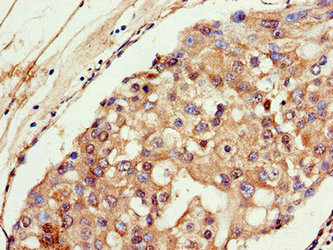

Immunohistochemistry of paraffin-embedded human breast cancer using CSB-PA16019A0Rb at dilution of 1:100